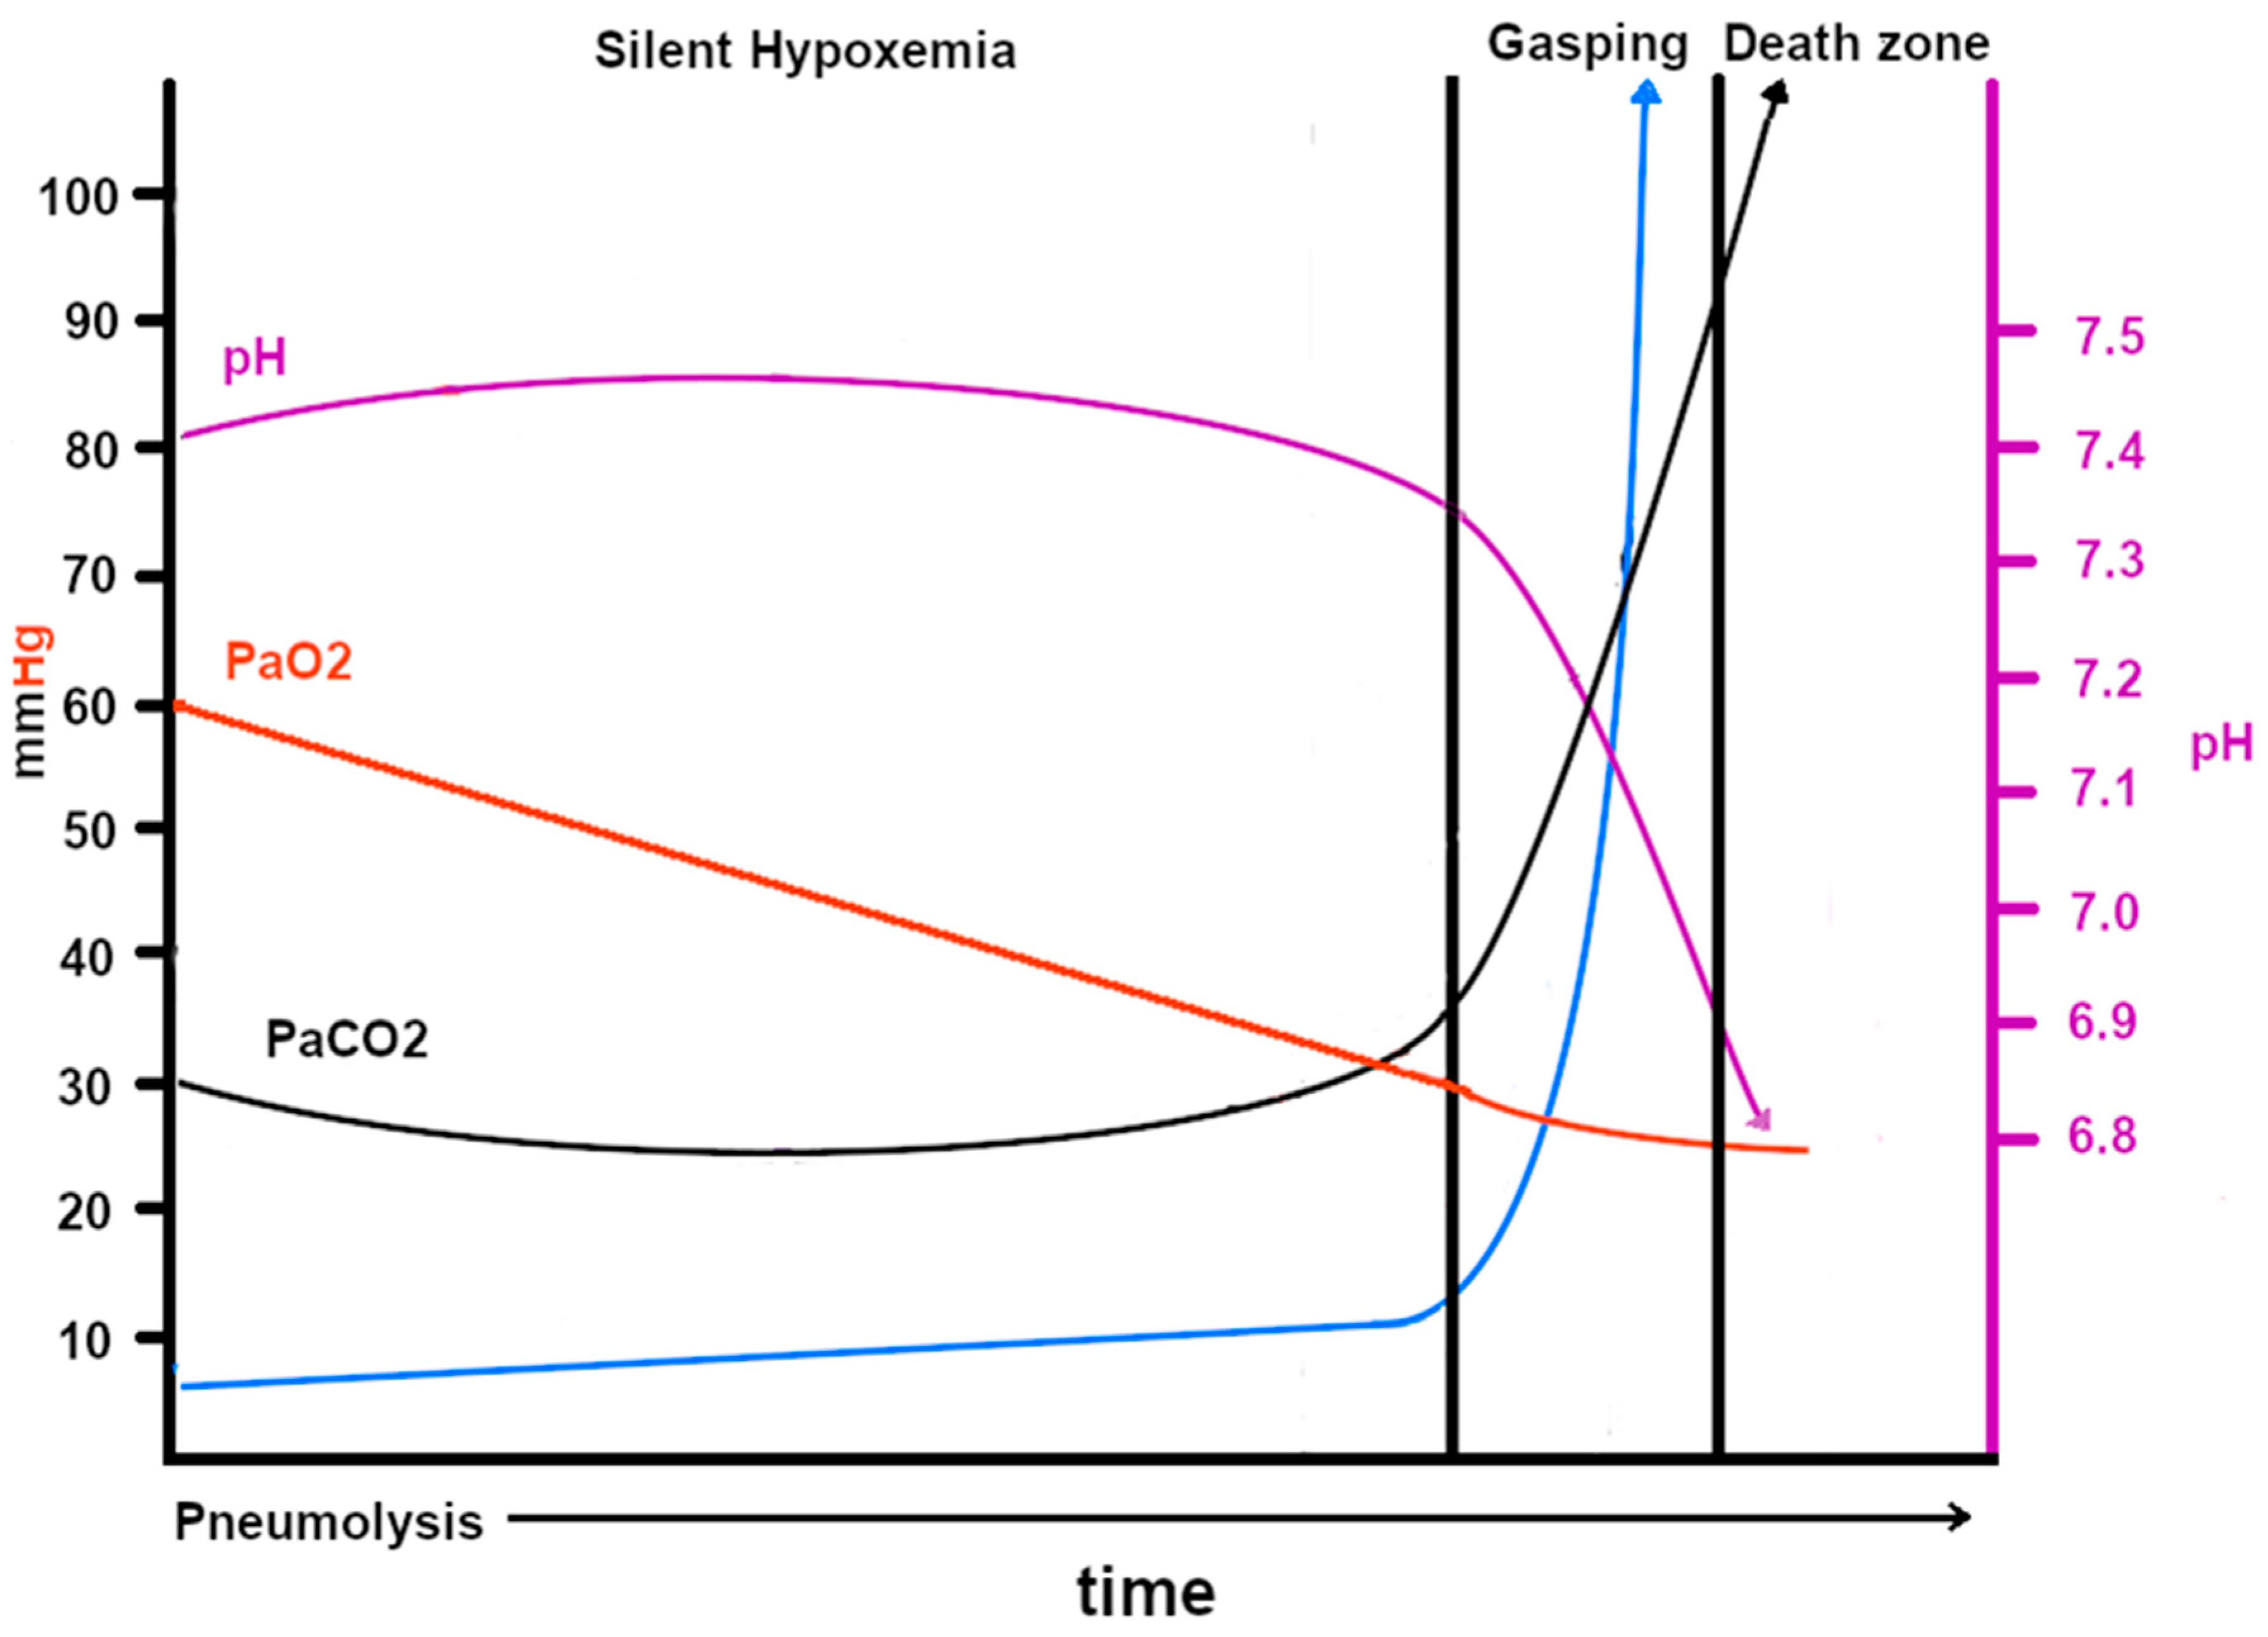

Figure 7.

This graph, developed by both Zubieta authors, shows the probable blood gases, acid–base, ventilation, and hypoxemia evolution in COVID-19 disease at sea level. Note that the pH scale is on the right and the PaO2, PaCO2 and ventilation scales are on the left. The CT scan images (courtesy of Centro de Estudios Tomográficos CET La Paz, Bolivia) show how, as the disease spreads throughout the lungs, the gas-exchange compromise increases, thereby reducing the oxygen transport through the alveolar–capillary membrane. The green, black, and yellow dots represent actual blood gases obtained from https://www.youtube.com/watch?v=_KMLW8eO0q0 (accessed on 28 December 2025) by Dr. Shiv Kumar Singh. The black and red dots are from [39].

COVID-19 patients often show a predominance of pneumolysis in the lower lobes of both lungs. The probable explanation may relate to aerodynamics and lung elasticity, which initially respond by distending the lower lobes on inhalation due to diaphragmatic contraction and the direct orientation of the main bronchi, thereby directing SARS-CoV-2 to the base of the lungs. COVID-19 lung injury involves direct viral epithelial cell damage and thrombotic and inflammatory reactions. There are differences between ARDS and COVID-19 lung injury in aspects of aeration distribution, perfusion, and pulmonary vascular responses [84]. It has been established that angiotensin-converting enzyme 2 (ACE-2) is the cellular receptor for severe acute respiratory syndrome–coronavirus (SARS-CoV) and the new coronavirus (SARS-CoV-2) [85]. SARS-CoV-2 enters type 2 pneumocytes [86], and since these cells are next to type 1 pneumocytes and sustain them, they are destroyed, and the whole alveolar structure is seriously compromised, as evidenced in several studies. The possible pathophysiological responses have been described in a paper entitled “Pneumolysis and Silent Hypoxemia” [18]. Figure 7 shows the pathophysiologic changes in COVID-19. Some newspaper interviews and publications in a local bulletin in La Paz, Bolivia, have informed the public about this new terminology and its implications [28].

However, as the disease progresses, all three hypoxia-producing conditions are present (diffusion, ventilation/perfusion inequality, and, above all, shunts), and it is for this reason that supplementary oxygen is unable to raise the SpO2 to normal levels (98% at sea level and 90% at 3500 m of altitude). Carbon dioxide (20 times more diffusible than oxygen) can still be adequately ventilated and expelled despite the significant reduction in the oxygen exchange surface (Figure 6). However, when the lung exchange surface is seriously compromised, the lung is unable to eliminate excess carbon dioxide [87], and this is when gasping occurs (Figure 6). It is essential to observe that the SpO2 falls linearly as the expansion of the pneumocyte invasion of SARS-CoV-2 evolves. We initially thought it would be a curve; however, based on actual blood gas data, it was concluded that it was most probably linear.

Originally, we also observed that there were not many changes in pH or PaCO2 in the “silent hypoxemia” phase [18], with mild hyperventilation as also described by [39]. The latter points out fundamental aspects; however, the whole picture is incomplete. In our experience, high-altitude residents at 3600 m (as at any altitude) actually live with a permanent “silent hypoxemia”. With this experience, we are able to propose the explanation of the baffling “silent hypoxemia” in COVID-19. It is for this reason that we postulate that during acute hypoxemia with the impossibility of raising PaO2 and SpO2, a fundamental solution in order to save lives would be to use of extracorporeal oxygenation [18] and the administration of erythropoietin.

The pathophysiology of COVID-19 at high altitude is shown in Figure 8, where the starting PaO2 is 60 mmHg at 3500 m. The descent to critical hypoxia is not as steep as at sea level. This could help explain the lower incidence of COVID-19-related deaths at high altitudes.

This graph shows the probable blood gases, acid–base, ventilation, and hypoxemia evolution in COVID-19 disease at 3500 m (12,000 ft) of altitude, where the normal PaO2 is 60 mmHg and the normal SpO2 is 88–92%. Notice that the gradual PaO2 decrease slope is much lower and is, hence, related to a higher tolerance to hypoxia than at sea level (with a lower PaCO2 = 30 mmHg), which becomes an advantage for survival until immunity ensues. The death rates from COVID-19 are much lower at high altitudes than at sea level. The blue arrow is ventilation.